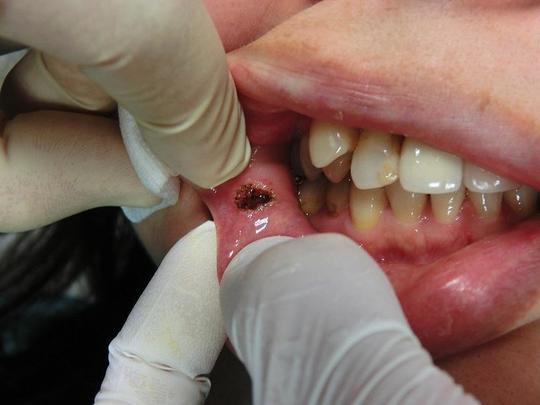

口腔内のイボ・できもの(線維腫・乳頭腫などの良性腫瘍)をCO2レーザー(炭酸ガスレーザー)で切除した症例。

線維腫、乳頭腫などは誤って粘膜を噛んでしまうと出現することが多く、またその部位を繰り返し噛んでしまい大きくなるケースもあります。

口唇の場合

術後

術後は口内炎のようになりますが、ほとんど痛みやしみたりしません。口内炎のような跡も1週間程度で小さくなってきます。